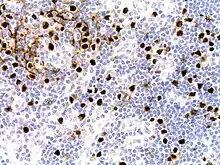

Micrograph of HHV8-associated Castleman's Disease showing LANA-1 positive lymphoblasts in a regressed germinal center and mantle zone. LANA-1 stain. | |

Formal criteria for the diagnosis of HHV-8-associated MCD have not been published; however, diagnosis requires enlargement of lymph nodes in multiple lymph node regions (typically confirmed with radiologic imaging), histologic changes consistent with HHV-8-associated MCD on biopsy of an enlarged lymph node, and confirmation of HHV-8 infection by LANA-1 lymph node staining or peripheral blood polymerase chain reaction for HHV-8.[6] HIV testing is useful for management, but a positive result is not necessary for to diagnose HHV-8-associated MCD.[2]

Staining with latency-associated nuclear antigen (LANA-1), a marker for HHV-8 infection, is typically positive.[11]